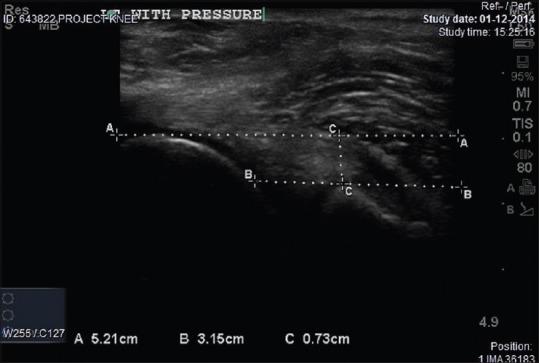

MATERIALS AND METHODS

In this study, we included the patients coming to orthopedics outpatient department with sign and symptoms of ACL injury. We performed functional USG of the injured and uninjured knee and noted the difference in translation, measured by USG. More than 1 mm of difference in translation of tibia on the affected side as compared to uninjured side is taken as significant. We compared our result with the findings of MRI. The study result of 130 patients revealed high sensitivity (81.65%) and high specificity (89%) in diagnosing ACL injury. The positive predictive value of the test was 97.8%, and the negative predictive value was 44%. The value of the difference of translation as 0.0001 was also statistically significant.

材料与方法

在本研究中,我们纳入了前来骨科门诊且有ACL损伤体征和症状的患者。我们对受伤和未受伤的膝关节进行了功能性USG检查,并记录了通过USG测量的平移差异。患侧胫骨与未受伤侧相比,平移差异超过1mm被视为有意义。我们将我们的结果与MRI的检查结果进行了比较。130例患者的研究结果显示,在诊断ACL损伤方面具有高敏感性(81.65%)和高特异性(89%)。该检查的阳性预测值为97.8%,阴性预测值为44%。平移差异值为0.0001在统计学上也具有显著性。